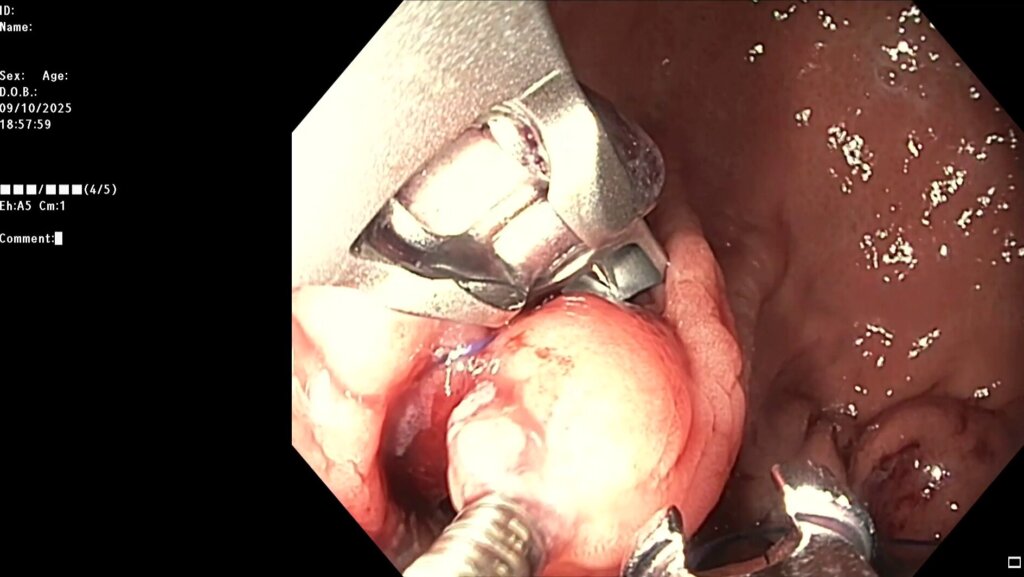

После предварительного обследования произведена операция: ESG + АПК (APC) свода; всего использовано 6 швов, время процедуры ≈ 120 минут.

Комбинированный метод представляет собой эндолюминальное ушивание желудка (формирование «рукава») с добавлением локальной аргоноплазменной коагуляции (АПК, APC — поверхностная неконтактная термальная абляция слизистой) в зоне свода желудка с целью индуцирования контролируемого фиброза и снижения секреции грелина. ESG выполняется перорально под визуальным контролем с использованием системы Overstitch;

Под видеоконтролем выполнена эндоскопическая рукавная гастропластика: сшивание стенок желудка при помощи аппарата Overstitch Boston Scientific по длине тела с целью уменьшения объёмов съедаемой пищи.